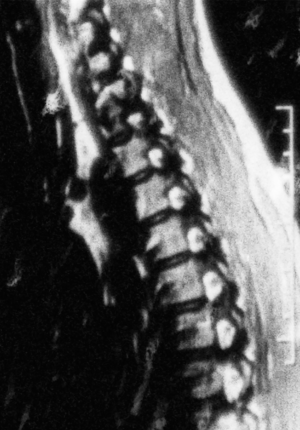

À travers des fragments sensoriels, ce film explore la douleur invisible d’une maladie rare qui creuse la moelle épinière et isole les personnes qui en souffrent. Malgré l’océan qui les sépare, trois femmes, mêlent leur parole pour partager leur expérience de la syringomyélie. Entre récits intimes et sensations physiques, ce documentaire expérimental nous plonge dans l’impact de cette douleur neuropathique sur le corps et la manière dont elle façonne la perception du monde.

Through sensory fragments, this film delves into the invisible pain of a rare disease that erodes the spinal cord and isolates those who suffer from it. Separated by an ocean, three women intertwine their voices to share their experience with syringomyelia. Blending intimate narratives and raw physical sensations, this experimental documentary immerses us in the impact of neuropathic pain on the body and the way it shapes one’s perception of the world.